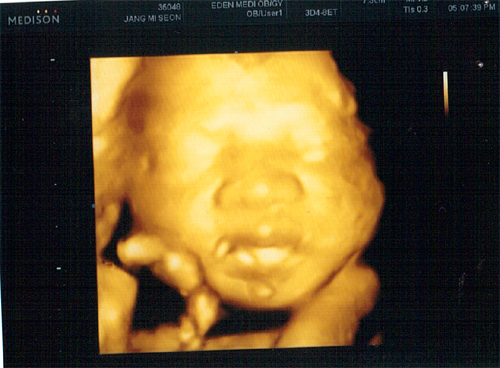

26주 4월 8일(금) 입체 초음파사진